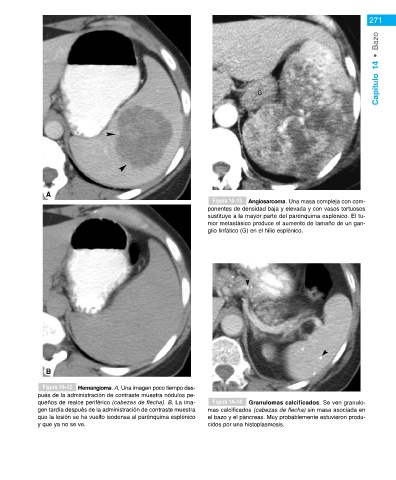

Figura 14–13 Angiosarcoma. Una masa compleja con com-

ponentes de densidad baja y elevada y con vasos tortuosos

sustituye a la mayor parte del parénquima esplénico. El tu-

mor metastásico produce el aumento de tamaño de un gan-

Metástasis gen del 50% de las metástasis esplénicas que se detec- glio linfático (G) en el hilio esplénico.

hallazgos del hemangioma en la TC incluyen: Figura 14–12 Hemangioma. A, Una imagen poco tiempo des-

pués de la administración de contraste muestra nódulos pe-

• Las lesiones pueden tener un aspecto quístico o queños de realce periférico (cabezas de flecha). B, La ima- Figura 14–14 Granulomas calcificados. Se ven granulo-

sólido en la TC sin contraste. Pueden ser únicas o gen tardía después de la administración de contraste muestra mas calcificados (cabezas de flecha) sin masa asociada en

múltiples. que la lesión se ha vuelto isodensa al parénquima esplénico el bazo y el páncreas. Muy probablemente estuvieron produ-

• Después de la administración de contraste los he- y que ya no se ve. cidos por una histoplasmosis.